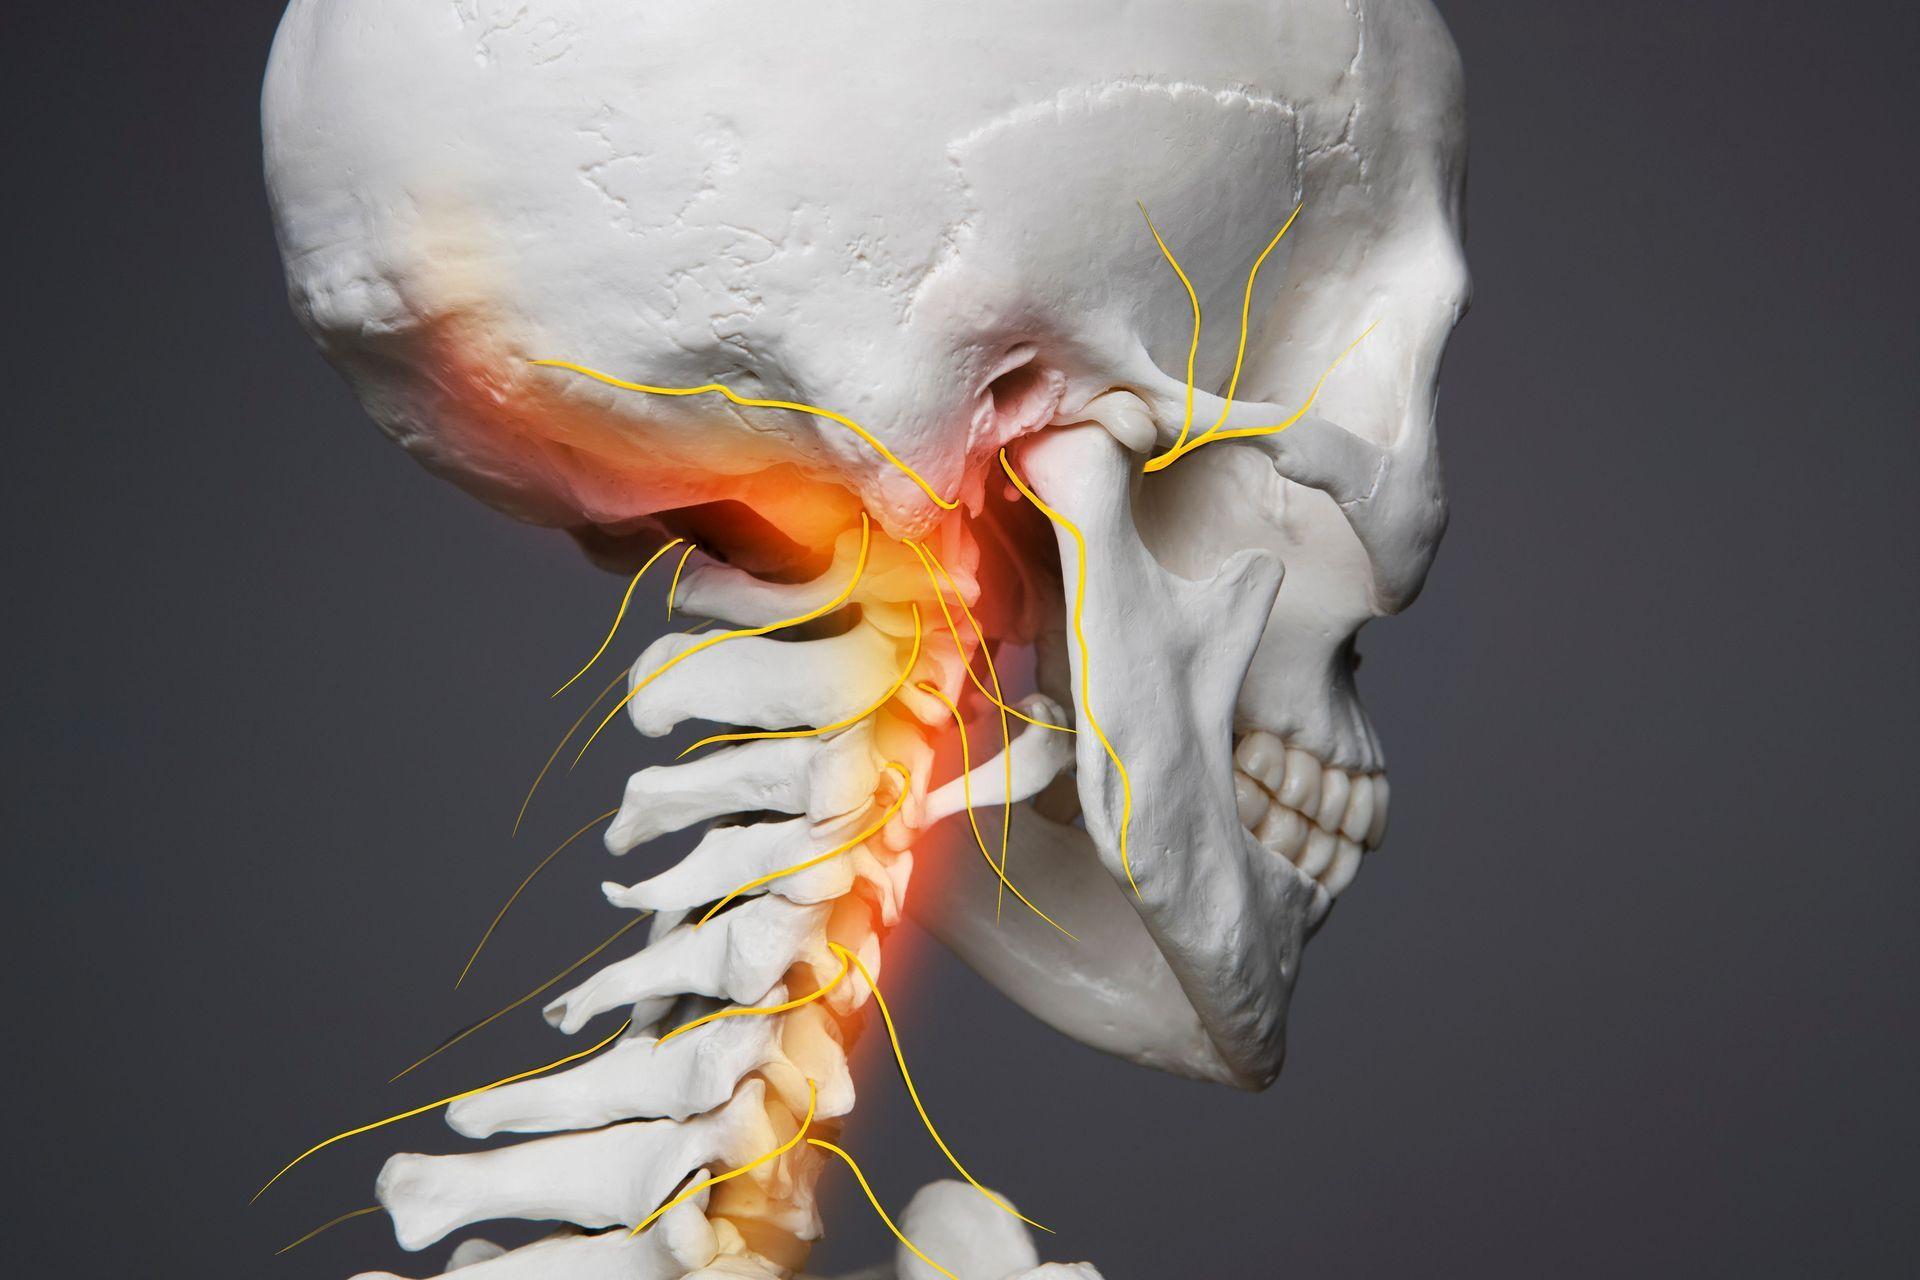

At Deuk Spine Institute, we don't just treat symptoms – we cure the source with our revolutionary Deuk Laser Disc Repair®, the world's most advanced laser spine surgery. With a 95% success rate and patients walking out pain-free within hours, we've redefined what's possible in spine care. Read our blog to learn more about root causes of pain and treatment solutions.